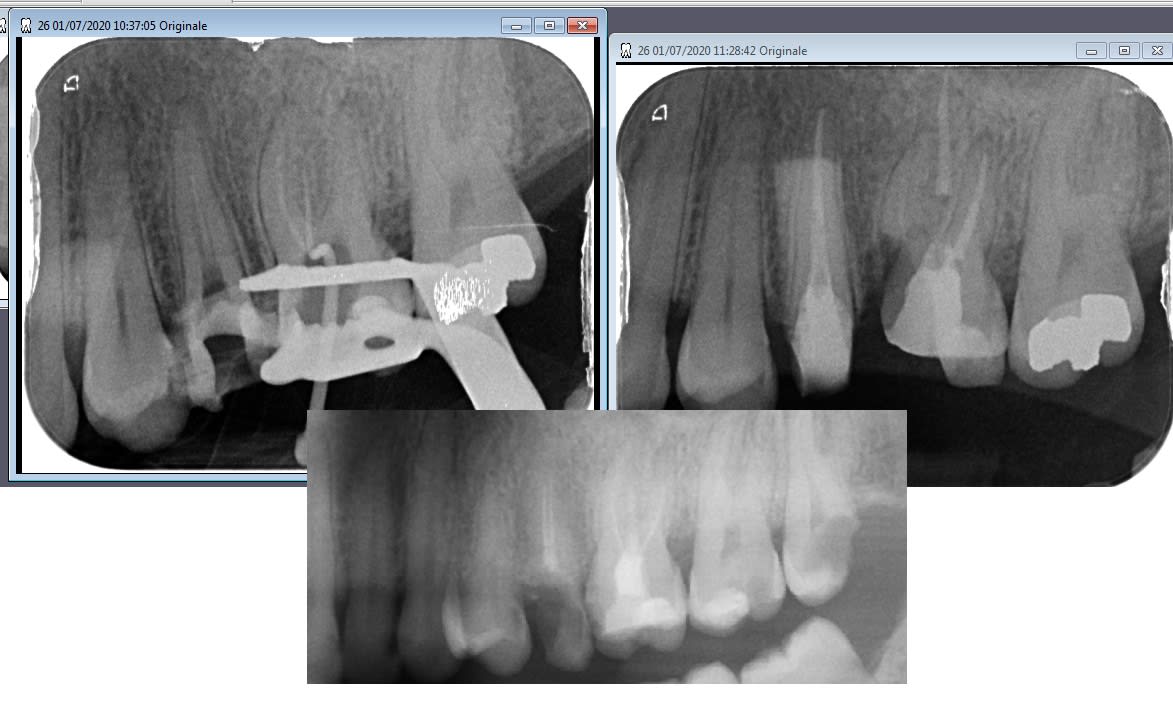

En cherchant à retrouver MV1 et 2 traités de manière symbolique, j'ai fait un très joli tout droit, dans la furcation. Décision prise d'amputer la mésio-vestibulaire dans la foulée, j'y ai laissé l'apex. Et quand je dit l'apex, c'est dans l'acception large, mettons la moitié apicale.

Tiens, revenons sur l'histoire pour analyser les conneries, et la manière de les rattraper.

Joint la pano pré op, la per-op (je l'ai dit ailleurs, si je prends une per op, c'est que quelque chose a merdé), et la post op.

On voit d'ailleurs sur la post op pourquoi je n'ai pas pu virer la MV, la séparation était tout simplement incomplète.

On note le délabrement presque juxta osseux de la 25. Ce qui va nous sauver, c'est l'absence d'empressement de la patiente. J'avais de toute manière prévu aujourd'hui de laisser la 25 avec son moignon à l'air libre, en large sous occ; j'en ai profité pour y filer un coup de fraise dans le sulcus pour favoriser l'égression dans les mois qui viennent. Le jour où j'irais chercher la MV, je ferais une plastie osseuse au passage avant de laisser cicatriser gentiment.

(évidemment, sur la perop, le cône n'est pas dans le palatin)

Suite de l'analyse: pourquoi le faux canal?

-CMU, pas de npc sur la désobturation, donc j'ai voulu réduire le temps passé. Bien fait pour ma gueule.

-j'ai conservé l'ouverture de chambre initiale, sans prendre le temps de me mettre à l'aplomb du canal.